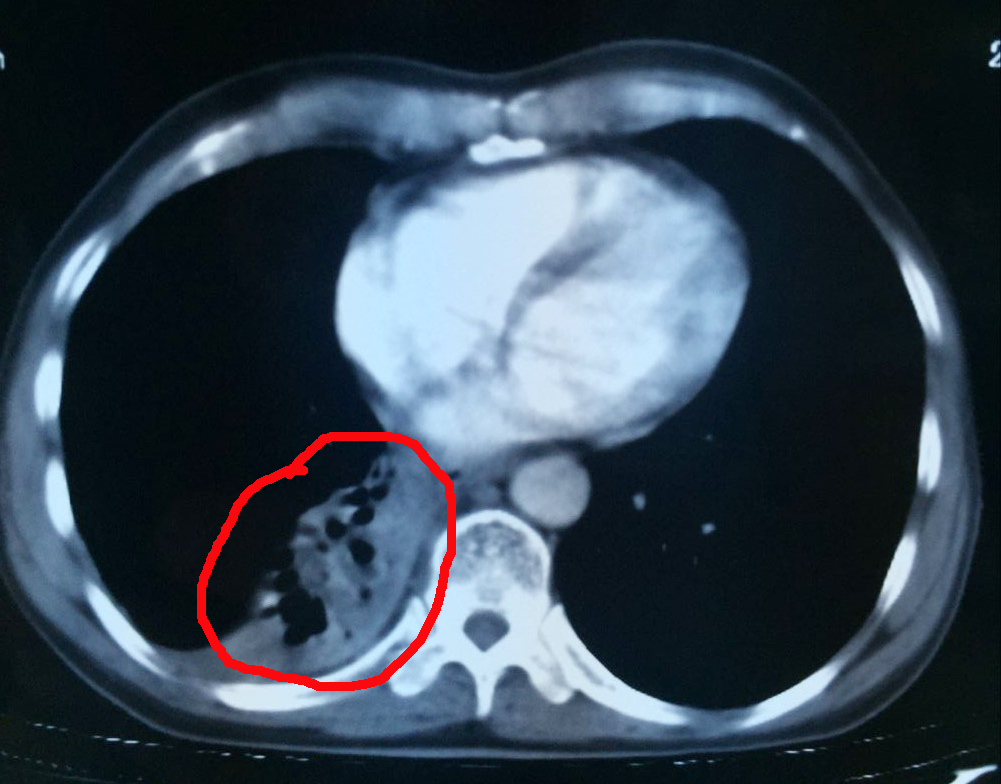

肿瘤治疗中